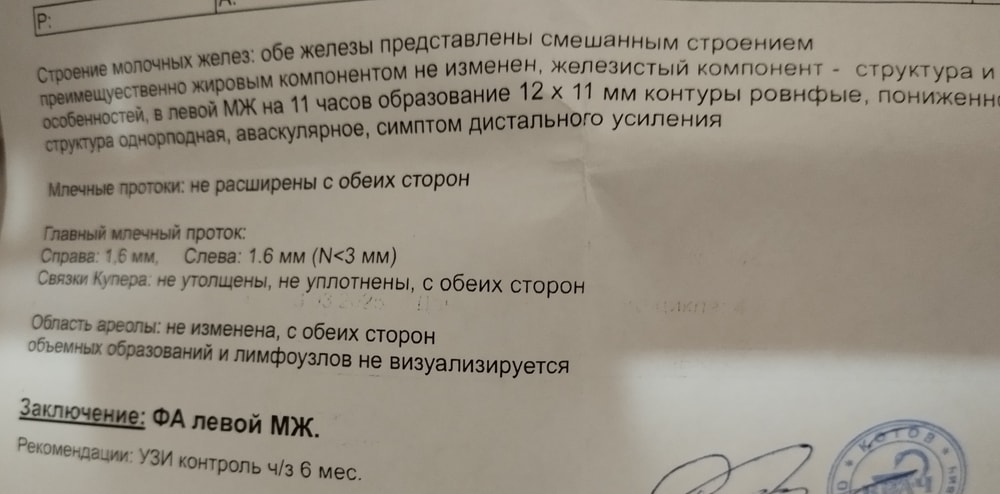

Сходила на узи, вроде бы по результатам все хорошо, но описание не вяжется с снимком. Написано, что контуры ровные, структура однородная, но по снимку этого не скажешь. Написано, что фиброаденома, но образование имеет ширину почти равную высоте и потому на "добро" не очень похоже. Конечно, я уже записалась переделать узи и к онкологу. Запись только на 5 апреля, очень переживаю((

Ольга , спасибо вам за ответ. Знаю, что частая штука. Сомневаюсь, что в данном случае это фиброаденома. По снимку не очень похоже